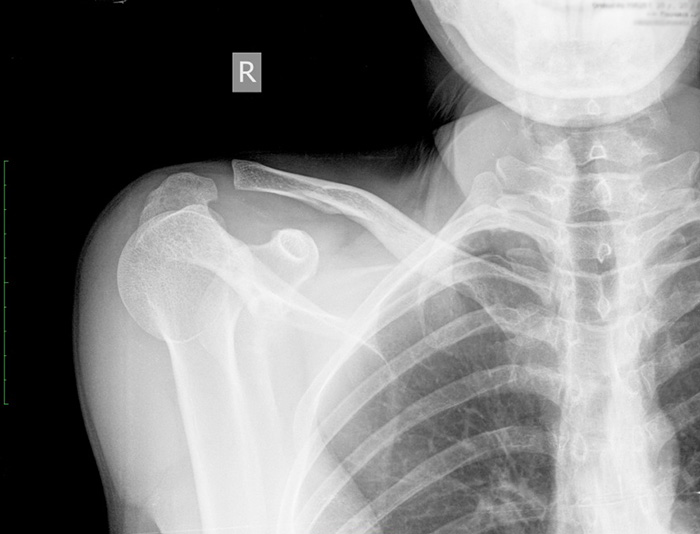

Переломы ключицы

Симптомы перелома трудно спутать с другими травмами, так как они возникают после травмирующих событий, которые пациент хорошо помнит: ударов, падений на выпрямленные руки или локти. Боль при переломах интенсивная, сопровождается отеком и синяками, а кость может изменить свое положение.

Вывихи и смещения

Вывих плечевого конца ключицы вызывает острую боль.

Грудинный конец ключицы, соединяющий её с грудной клеткой, может быть повреждён в результате травм, падений или ударов. Эта патология встречается редко и проявляется следующими симптомами:

- сильный отёк;

- выпячивание или западение ключицы;

- боль и покраснение.

Акромиальный конец ключицы соединён с лопаткой с помощью нескольких связок. При их разрыве пациент испытывает острую боль, и возможность поворота плеча резко ограничивается.

Повреждения акромиально-ключичного сустава

Этот структурный элемент расположен в области пересечения лопатки и ключицы. Травма возникает чаще всего после удара или падения. Она вызывает сильную боль, отечность, повышенную чувствительность, а также смещения и выступы кости. Лечение травмы возможно как оперативным путем, так и с помощью плечевой скобы для стабилизации.